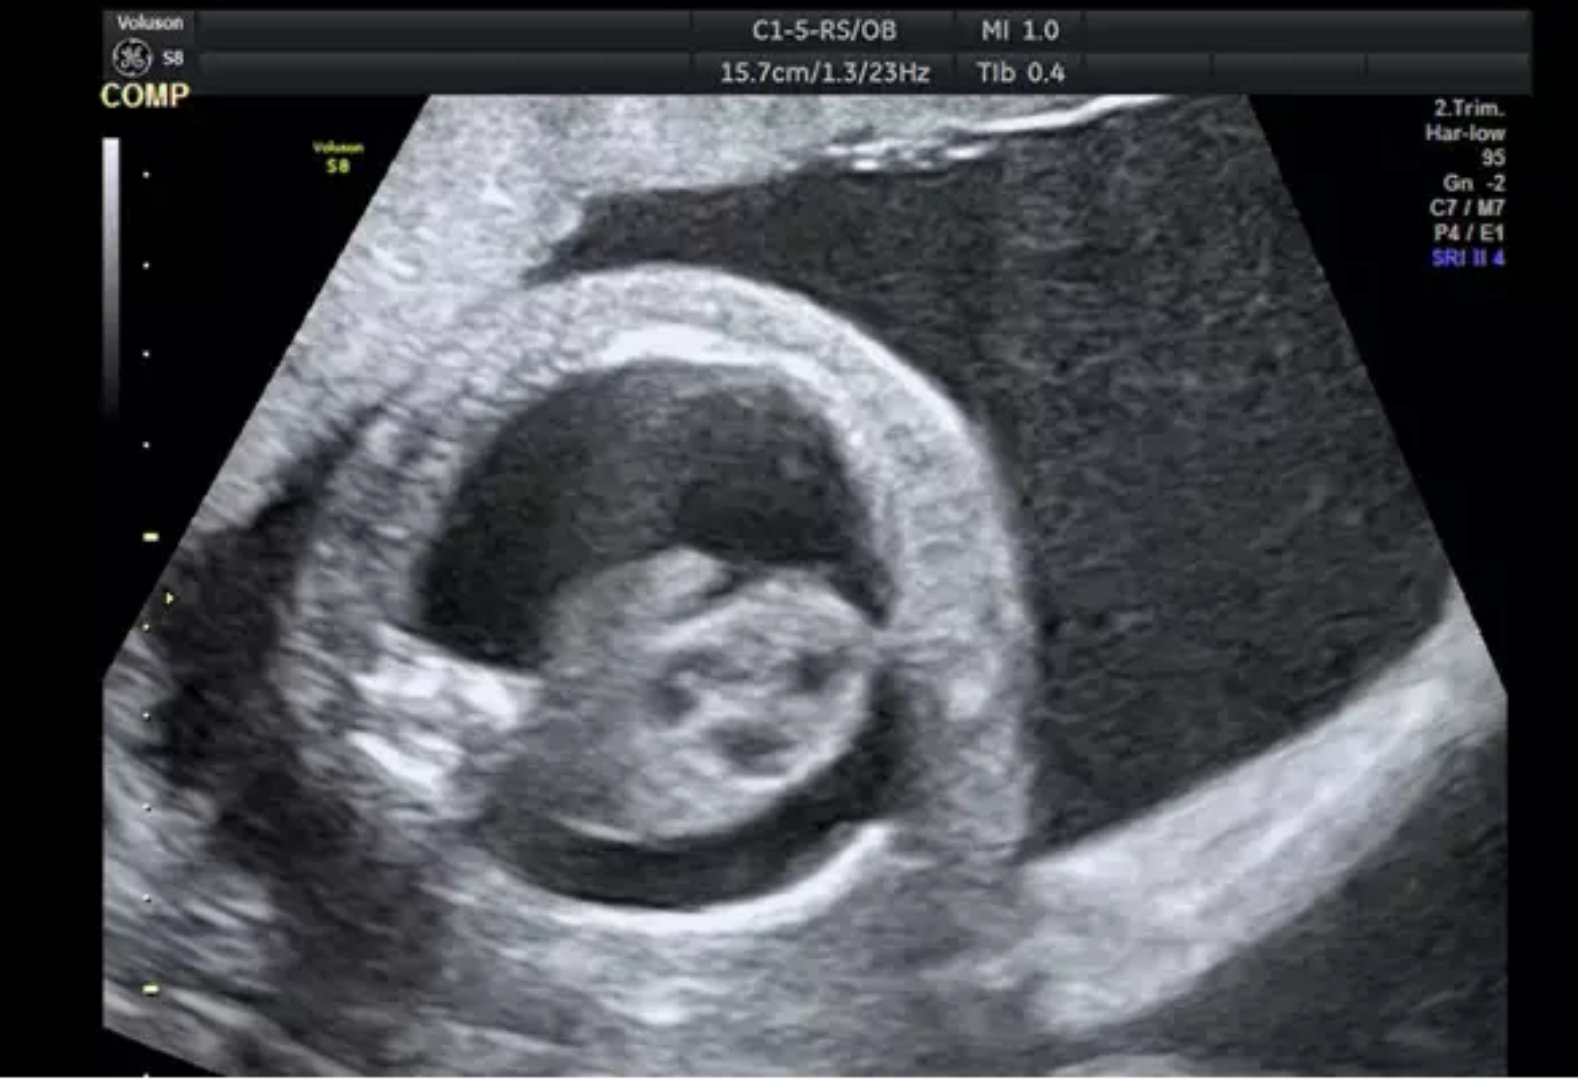

2018年7月中旬,由河南省人民医院产科主任武海英、产科刘侃医生、陶涛医生和超声科王睿丽主任组成的胎儿医学团队对一位孕16周、双胎之一无心序列的患者实施了射频消融减胎术,成功地减去无心畸胎,另一胎儿正在腹中健康地成长,而此项手术已是河南省人民医院产科第三十例射频减胎术。

射频消融技术是通过超声引导,将电极针置入异常胎儿体内脐血管,通过高热使胎儿的脐血管凝固阻断胎儿供血,导致异常胎儿死亡的新技术。与其他选择性减胎术相比,射频消融减胎术更为安全可靠、时间更短、过程更直观可视。射频消融减胎术的适应征包括:单绒毛膜多胎妊娠者、双胎反向动脉灌注序列征、单绒毛膜双胎其中一胎合并致死性畸形、选择性生长受限II型与III型、双胎输血综合征。